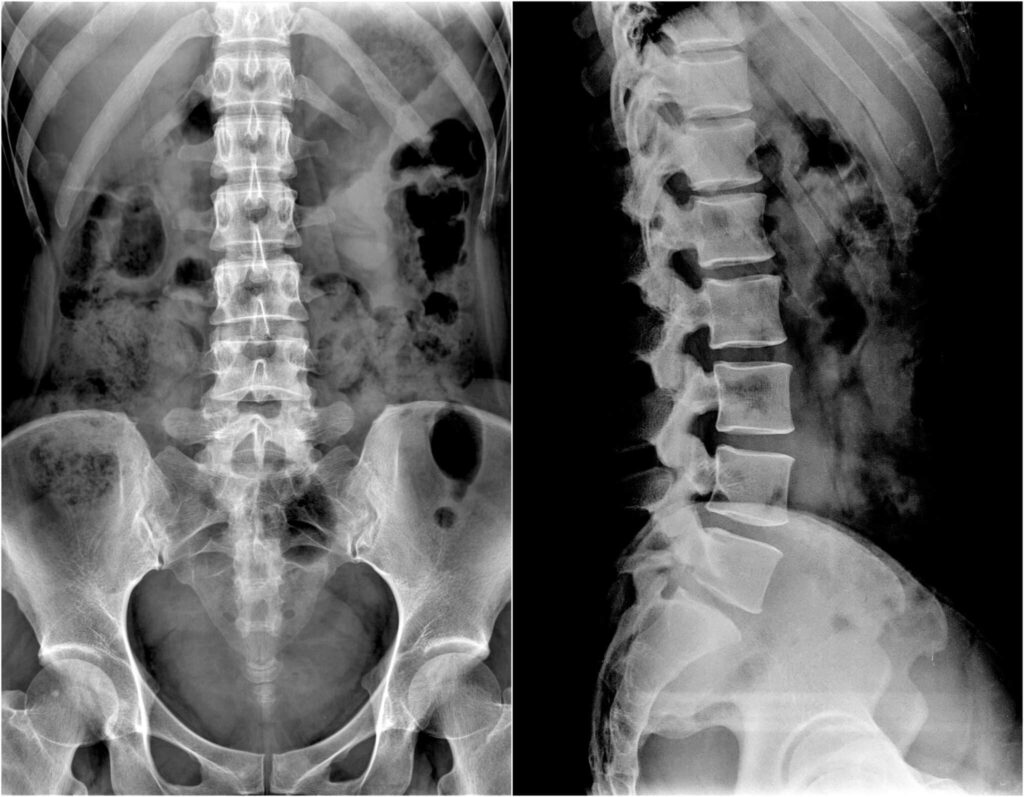

B. Badania Obrazowe: Rentgen, MRI, Tomografia Komputerowa

- Rentgen: Rentgen kręgosłupa może pomóc lekarzowi w wykryciu ewentualnych zmian degeneracyjnych, złamań, zwyrodnień stawów czy przemieszczeń kręgów. Jest to często stosowane badanie obrazowe wykonywane w pierwszej kolejności.